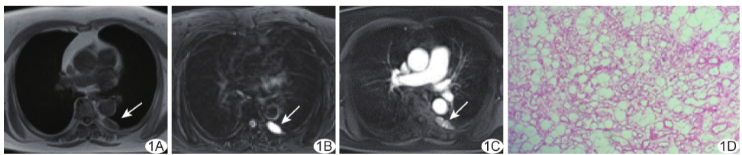

患者女,66岁,持续性背部隐痛1月余;既往体健。查体及实验室检查未见明显异常。胸部MRI:后纵隔偏左4.8 cm×2.5 cm×1.7 cm肿块,边界清晰,T1WI呈中心低信号、边缘等-稍高信号(图1A),反相位T1WI信号减低,脂肪抑制T2WI呈高信号(图1B);增强扫描动脉期肿块明显不均匀强化(图1C),延迟期中央强化增强;考虑为神经鞘瘤或海绵状血管瘤

行胸腔镜下纵隔肿物切除术,术中见肿物位于第5~6肋间隙水平脊柱左旁,表面血管丰富。术后病理:光镜下见成熟脂肪细胞,毛细血管不均匀分布于其内(图1D);免疫组织化学:AE1/AE3(-),CD34(+),CD31(+),HMB45(-),S-100(少许+),SMA(+),Ki-67(1%+),D2-40(-)。病理诊断:(后纵隔)血管脂肪瘤。本例报道经医院伦理委员会批准(2024-021)。

图1 原发性后纵隔血管脂肪瘤。A.胸部轴位MR T1WI;B.胸部轴位MR脂肪抑制T2WI;C.胸部轴位MR动脉期T1WI;D.病理图(HE,×100)(箭示病灶)

本例原发性后纵隔血管脂肪瘤较为罕见,T1WI呈等-稍高信号,脂肪抑制T2WI呈高信号,增强后病灶不均匀明显强化,提示其内脂肪含量少而血管较多,术中出血风险较高。